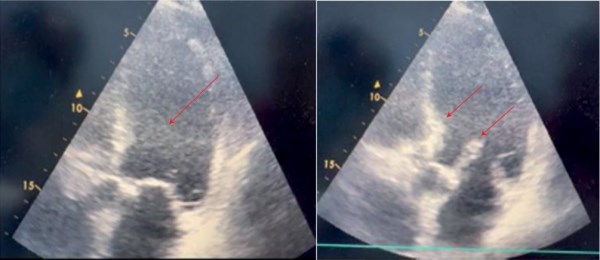

• Применение внутрисосудистого ультразвукового исследования (ВСУЗИ) позволило своевременно диагностировать протрузию бляшки через стент, не видимую ангиографически.

• Интраоперационный контроль с помощью ВСУЗИ обеспечил индивидуальный выбор тактики и предотвращение инсульта.

• ВСУЗИ подтвердило устранение протрузии и аде­кватное прилегание стента после серии бал­лонных дилатаций.

• Представленный случай подчёркивает стратегическое значение ВСУЗИ в безопасном проведении каротидного стентирования.

Каротидная ангиопластика со стентированием (КАС) является альтернативой хирургическому лечению у пациентов с высоким операционным риском при каротидной эндарэктомии. Согласно результатам крупного рандомизированного контролируемого исследования CREST (Carotid Revascularization Endarterectomy versus Stenting), существенных различий в частоте инсультов, инфарктов и смертей в группе КАС и каротидной эндарэктомии в отдаленном периоде нет. Однако значительное количество осложнений в группе КАС связано именно с перипроцедуральным периодом. Безопасность КАС напрямую зависит от технической успешности вмешательства и минимизации риска церебральной эмболии. Несмотря на использование эмболопротективной защиты в 100% случаев, профилактика инсульта остается актуальной проблемой. На примере клинического случая продемонстрировано влияние интраоперационного внутрисосудистого ультразвукового исследования (ВСУЗИ) на тактику вмешательства и профилактику осложнений при КАС, а также предложен алгоритм действий при интраоперационной протрузии бляшки.

Представленный клинический случай подтверждает, что ВСУЗИ является не просто диагностическим, а стратегическим инструментом, позволяющим индивидуализировать лечение на всех этапах КАС. Рутинное применение ВСУЗИ для оценки морфологии бляшки, интраоперационного контроля и управления осложнениями способно существенно повысить безопасность процедуры. Предложен алгоритм ведения пациентов с протрузией бляшки.